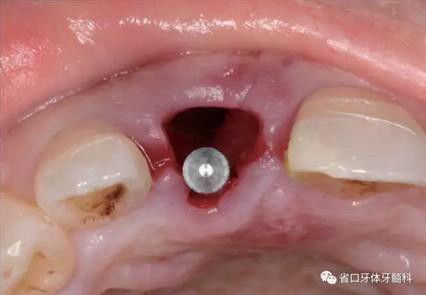

(2)制備臨時(shí)冠:術(shù)后當(dāng)天取模轉(zhuǎn)移,送工廠以Zimmer®多功能 攜帶體為臨時(shí)基臺(tái)制備臨時(shí)修復(fù),獲得舌隆突開(kāi)孔螺絲固位的烤塑臨時(shí) 冠。將其就位于口內(nèi)種植體,調(diào)整正中、前伸及側(cè)方咬合無(wú)接觸,加力 10~15N·cm,可見(jiàn)即刻修復(fù)體良好地支持齦緣及牙齦乳頭結(jié)構(gòu)。

圖22 臨時(shí)冠就位前袖口檢查

圖23 就位臨時(shí)冠